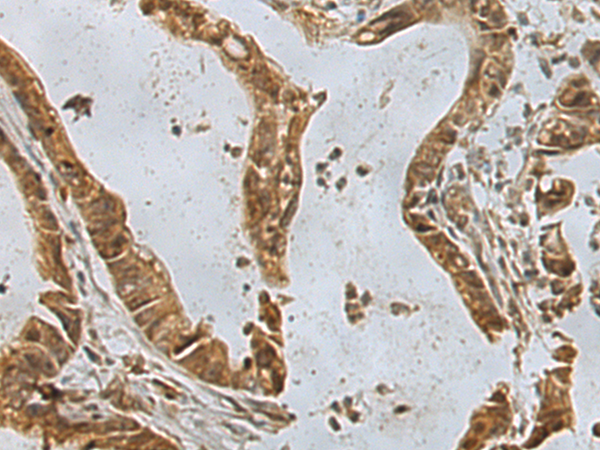

分类: 科研抗体货号: P10037别名: PP2CB; PP2CBETA; PP2C-beta; PPC2BETAX; PP2C-beta-X应用: IHC反应种属: Human